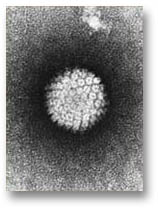

| 06:53, 23 October 2018 | Hpvirus.jpg (file) |  |

39 KB | Drtbalu | |